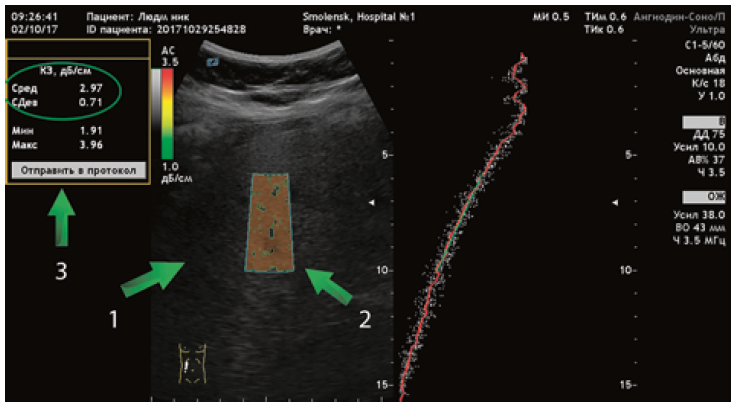

7-й этап. Ультразвуковая стеатометрия печени на аппарате «БИОСС Ангиодин Соно-П/Ультра» (Россия) с визуальной и количественной оценкой коэффициента затухания ультразвуковой волны (дБ/см) (рис. 1).

Рис. 1. Методика проведения ультразвуковой стеатометрии

Примечание. 1 — печень, 2 — активная зона измерения, 3 — количественный показатель стеатометрии (коэффициент затухания ультразвуковой волны).

Исследование выполнялось в положении пациента лежа на спине с отведенной за голову рукой. Измерение проводилось натощак, датчик устанавливался в VI–VIII межреберье по средней подмышечной линии [14, 15]. Для определения выраженности стеатоза использовалась шкала (дБ/см), коррелирующая со степенью стеатоза по данным биопсии печени.